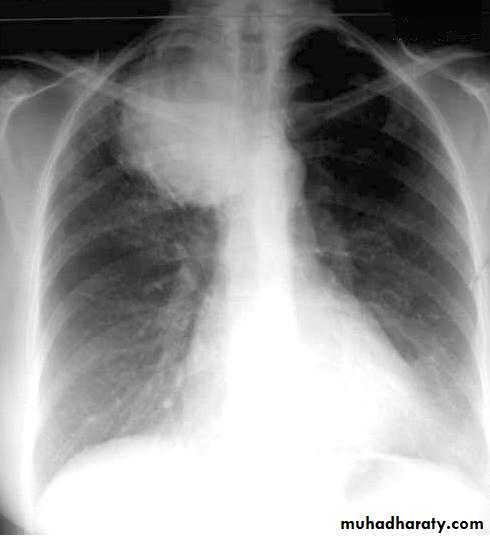

X-ray of pleural effusion

Pleural effusion